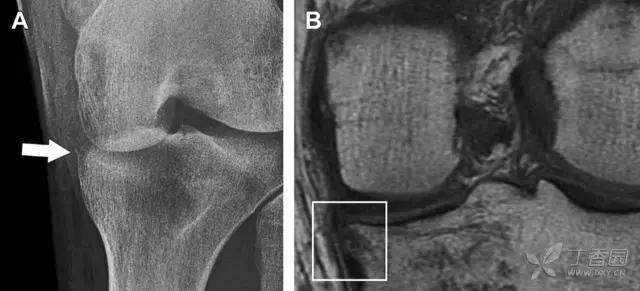

(1)Segond 骨折

是发生在胫骨平台外侧的垂直撕脱性骨折。这种骨折在前后位 X 线片上显示最佳。屈曲位时膝关节受到内旋*力暴**作用,导致皮质骨撕脱性骨折,这种骨折常发生在运动员身上。

常引起股骨内髁和胫骨平台后内侧骨挫伤,75%~100% 的患者伴前交叉韧带断裂,33% 的患者伴外侧半月板损伤。

一位足球运动员的 Segond 骨折。A 正位片示关节线下方胫骨外侧皮质撕脱(箭头)。B MRI 冠状位 T1 加权像示附着于髂胫带的骨折碎片(空箭头)(来源:Radiol Clin N Am 53 (2015) 737–755,YU,Ohio)